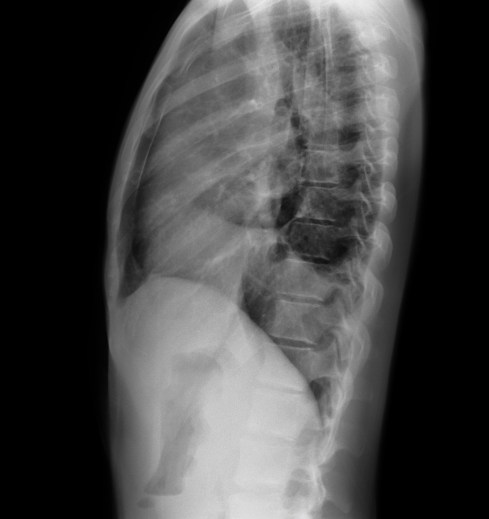

CASO: Febrícula y tos de 4 días de evolución.

Hallazgos:

- En la placa PA se observa una asimetría en los hilios pulmonares, el hilio izquierdo tiene una densidad aumentada.

- Tras examinar la placa lateral se observa un aumento de densidad en la columna que puede ser compatible con una condensación, es el signo de la desnificación vertebral.

SIGNO DE LA DENSIFICACIÓN VERTEBRAL: En la radiografía lateral normal, la densidad de la columna torácica tiende a disminuir desde la parte superior hasta el diafragma; la alteración de ese patrón por la presencia de una densidad superpuesta a la columna, indica la existencia de una consolidación pulmonar. Este signo adquiere especial valor cuando en la proyección posteroanterior la consolidación está oculta en el espacio retrocardíaco o en la base pulmonar.